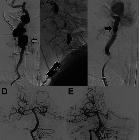

Treatment of

Extracranial Vertebral Aneurysm Associated with Two Intracranial Aneurysms—A Case Report: Figure 1. Preoperative angiograms. Upper-left corner: right carotid angiogram, anteroposterior projection, revealing a round aneurysm located on the proximal segment of the middle cerebral artery. Upper-right corner: left vertebral angiogram, anteroposterior projection, showing an irregular end-basilar aneurysm. Lower-left corner: left vertebral angiogram, left anterior oblique projection, demonstrating an aneurysm on the cervical segment of the artery (V2 segment). Lower-right corner: left vertebral angiogram, lateral projection, showing the vertebral aneurysm and the spinal collateral artery (arrow).